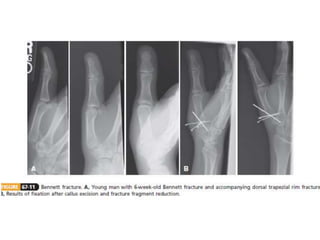

Carpometacarpal (CMC) Fractures

• The normal ROM at the thumb CMC joint

• 50 degrees of flexion-extension

• 40 degrees of abduction-adduction

• 15 degrees of pronation-supination.

Carpometacarpal (CMC) Fractures •The normal ROM at the thumb CMC joint • 50 degrees of flexion-extension • 40 degrees of abduction-adduction • 15 degrees of pronation-supination.